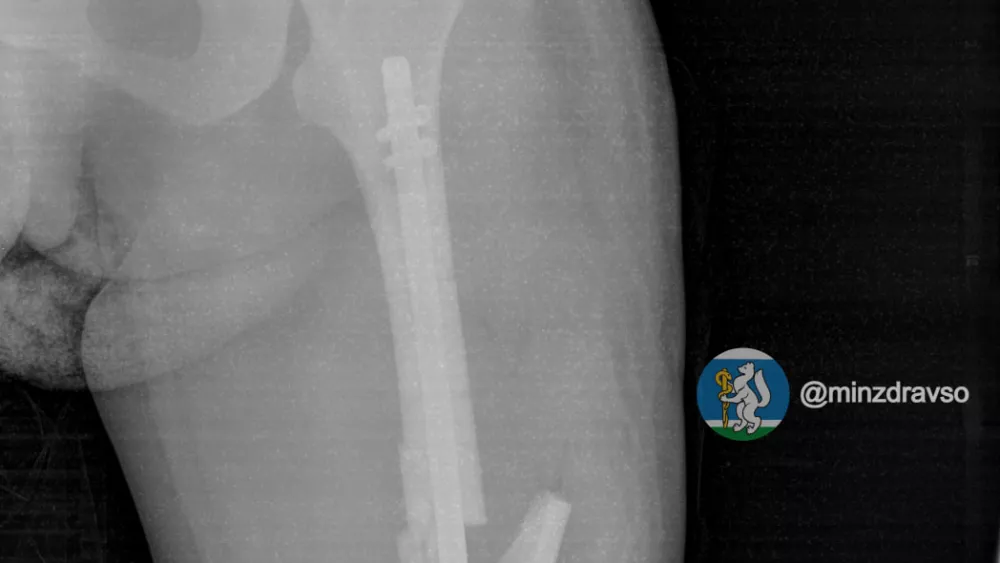

В первую же операцию врачи зафиксировали отломки кости и установили аппарат внешней фиксации, чтобы стабилизировать состояние. Спустя неделю, когда состояние пациентки улучшилось, была проведена повторная операция по замене внешнего аппарата на внутренний фиксатор с помощью современного метода блокирующего интрамедуллярного остеосинтеза. После почти двух недель лечения в травматологической больнице пациентку перевели в роддом для дальнейшего наблюдения за беременностью.

Фото: телеграм-канал "Здоровье уральцев"